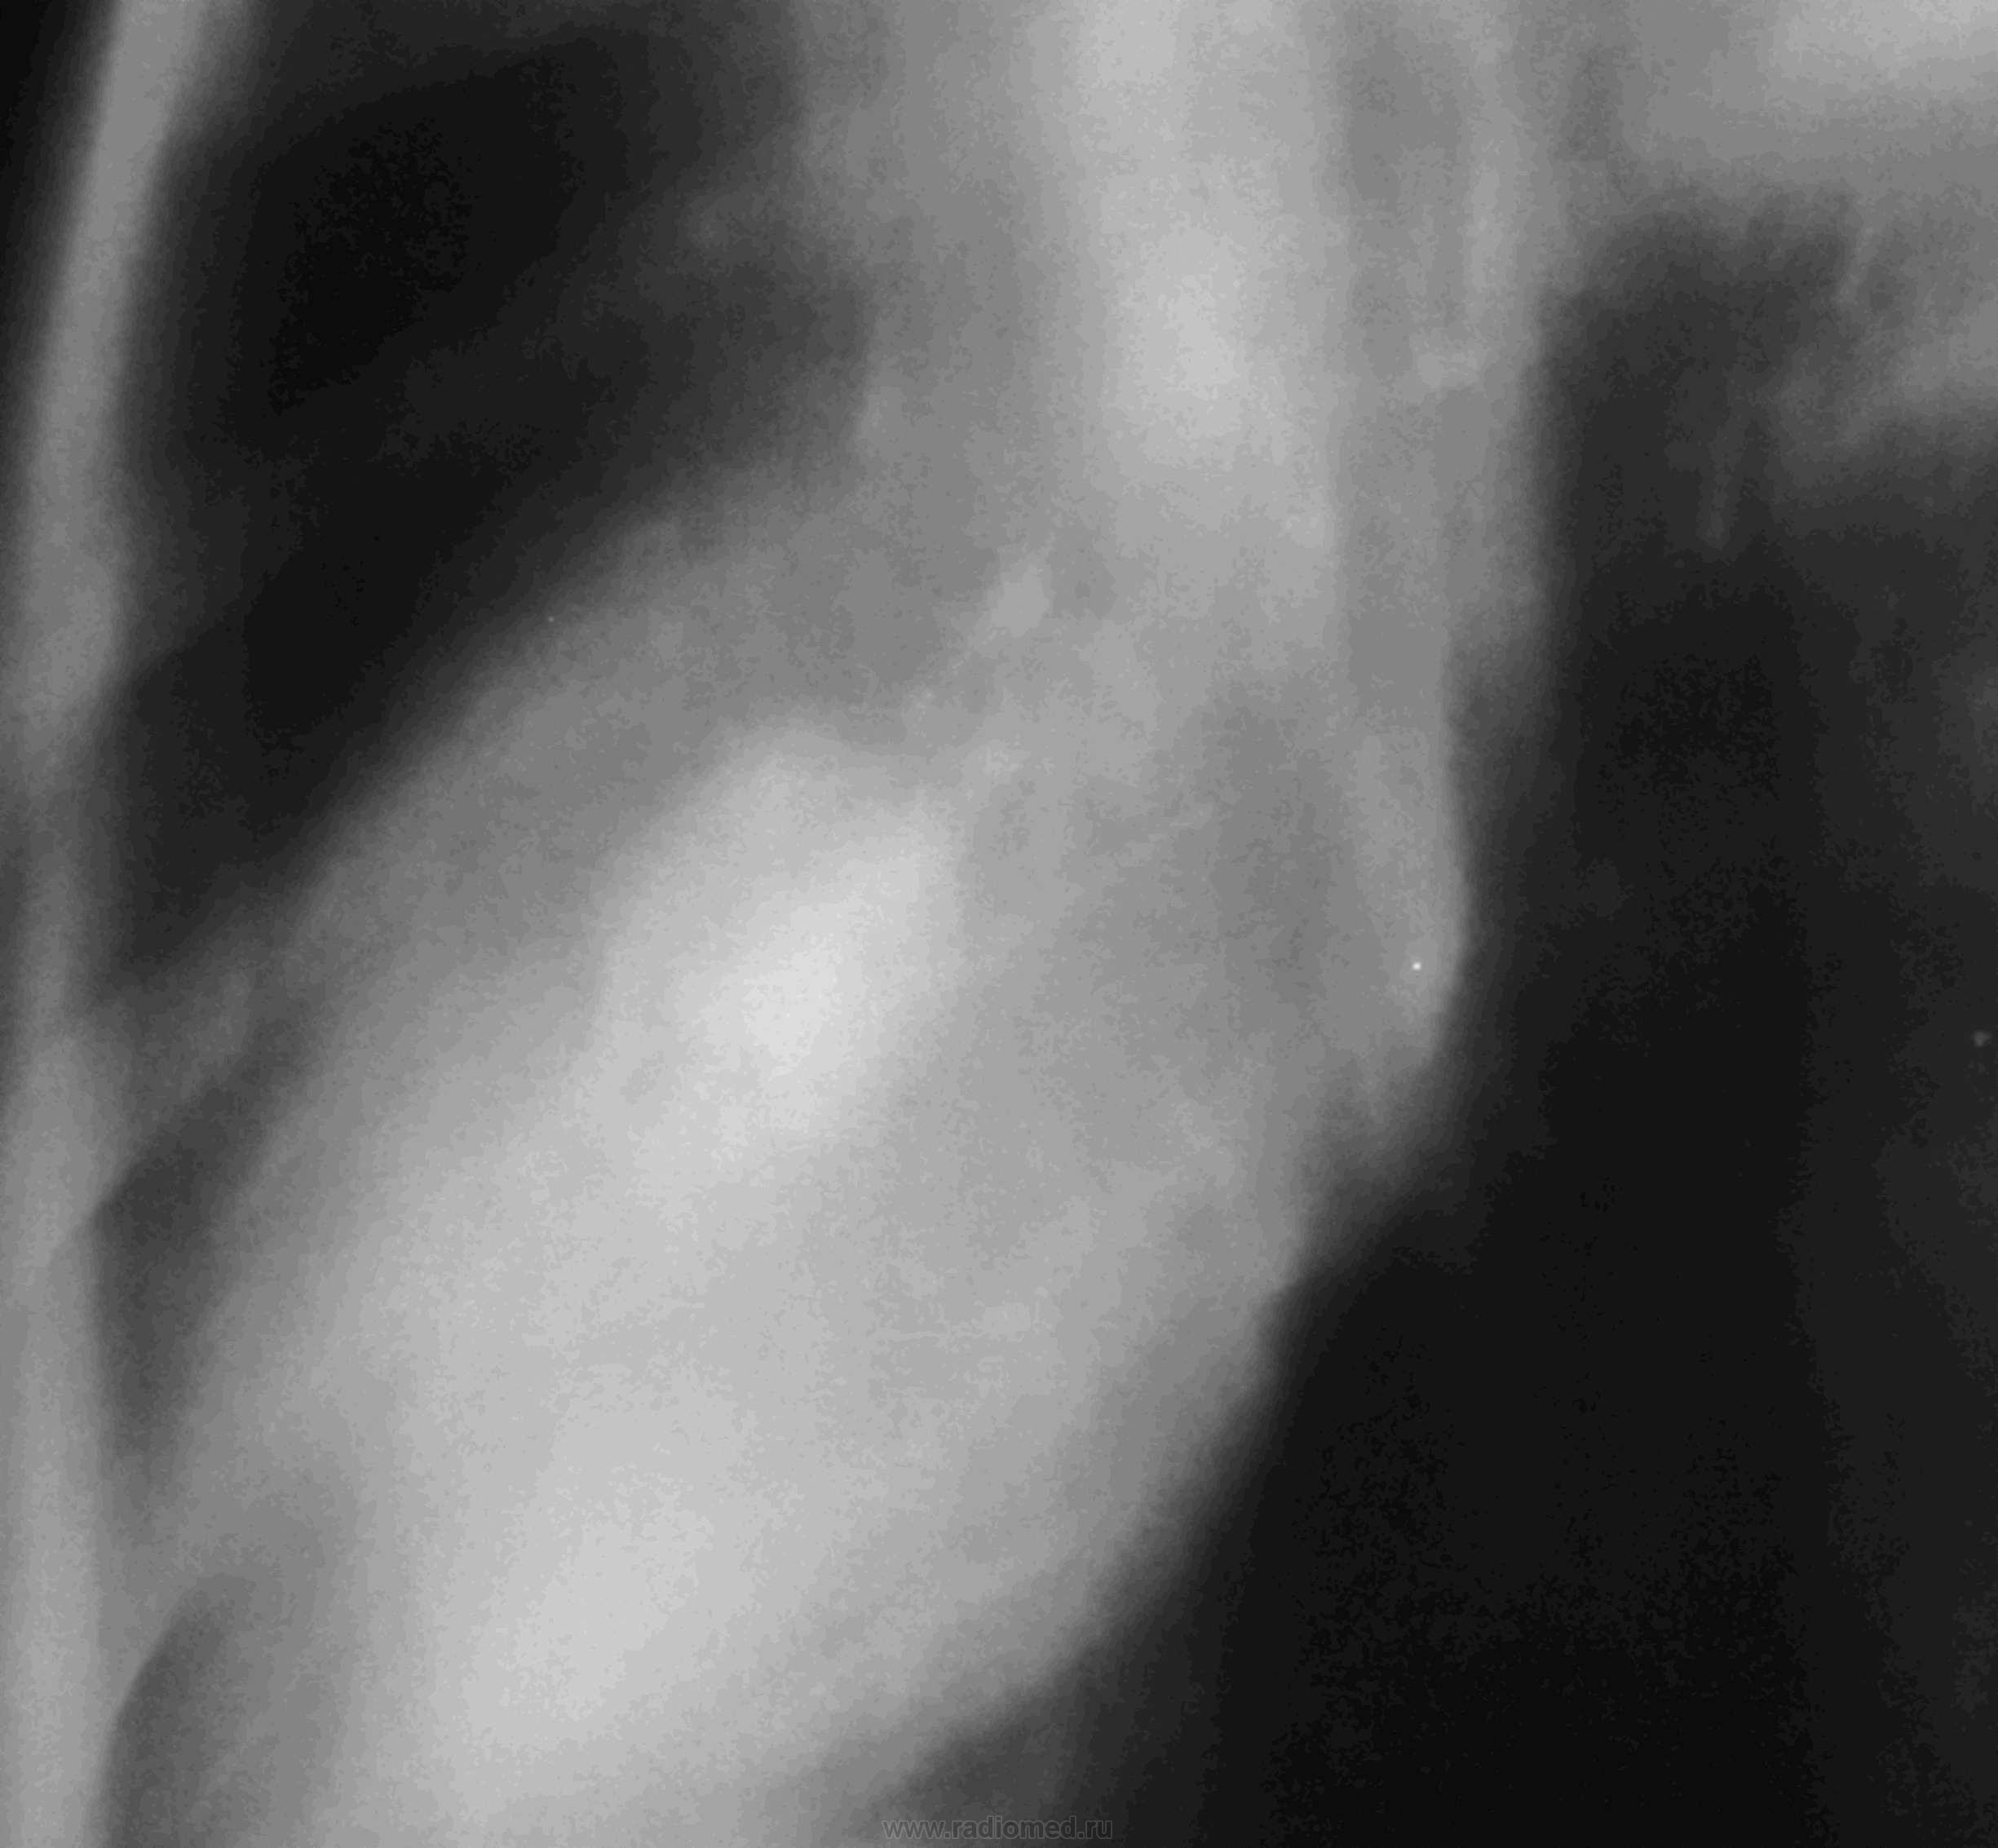

Молодой человек поступил в инфекционное отделени с тонзилитом. В день поступления флю - норма. Явления тонзилита прошли, но температура не снижалась. Сделали повторную флю и выставили пневмонию. Выставляю флюорограммы с интервалом в 1 неделю. Данные изменения держатся месяц без како-либо динамики. В анализах только повышенное СОЭ, колеблется от 20 до 38. В плане КТ.

Молодому человеку 20 лет. Снимки разместил по порядку с периодичностью в неделю. С момента поступления прошло полтора месяца. За это время, после инфекционного отделения, лечился в туберкулёзном, а после в пульмонологии (до настоящего времени).Последние рентгенограммы сделаны 2,04., а томограммы 4.04. По поводу кругляшки, особенно после туб.отд., думаю, что может выскочить и ТБЦ. Такое уже было, правда там был распад.

Какой интересный междолевой плеврит.

Левосторонняя S4-S5 пневмония, осложненная абсцедированием.По пятому по счету снимку явно на фоне инфильтрации видны зоны распада.А впоследствии и абсцесс сформировался-ТМГ тому подтверждение.Отдавайте торакалистам .